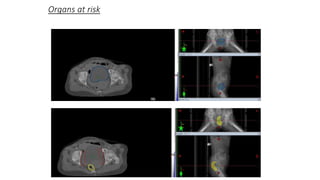

CTV TOTAL

PTV

Organs at risk